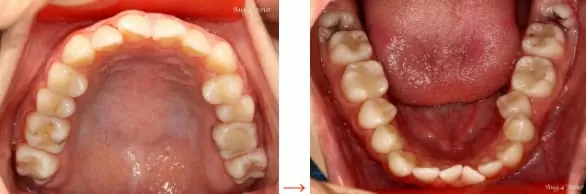

病患上排門牙及左上區牙齒不整齊,下排門牙及左下區牙齒排列不整齊,不僅影響整體臉形的美觀也造成牙齒上、下咬合不舒適及磨損。